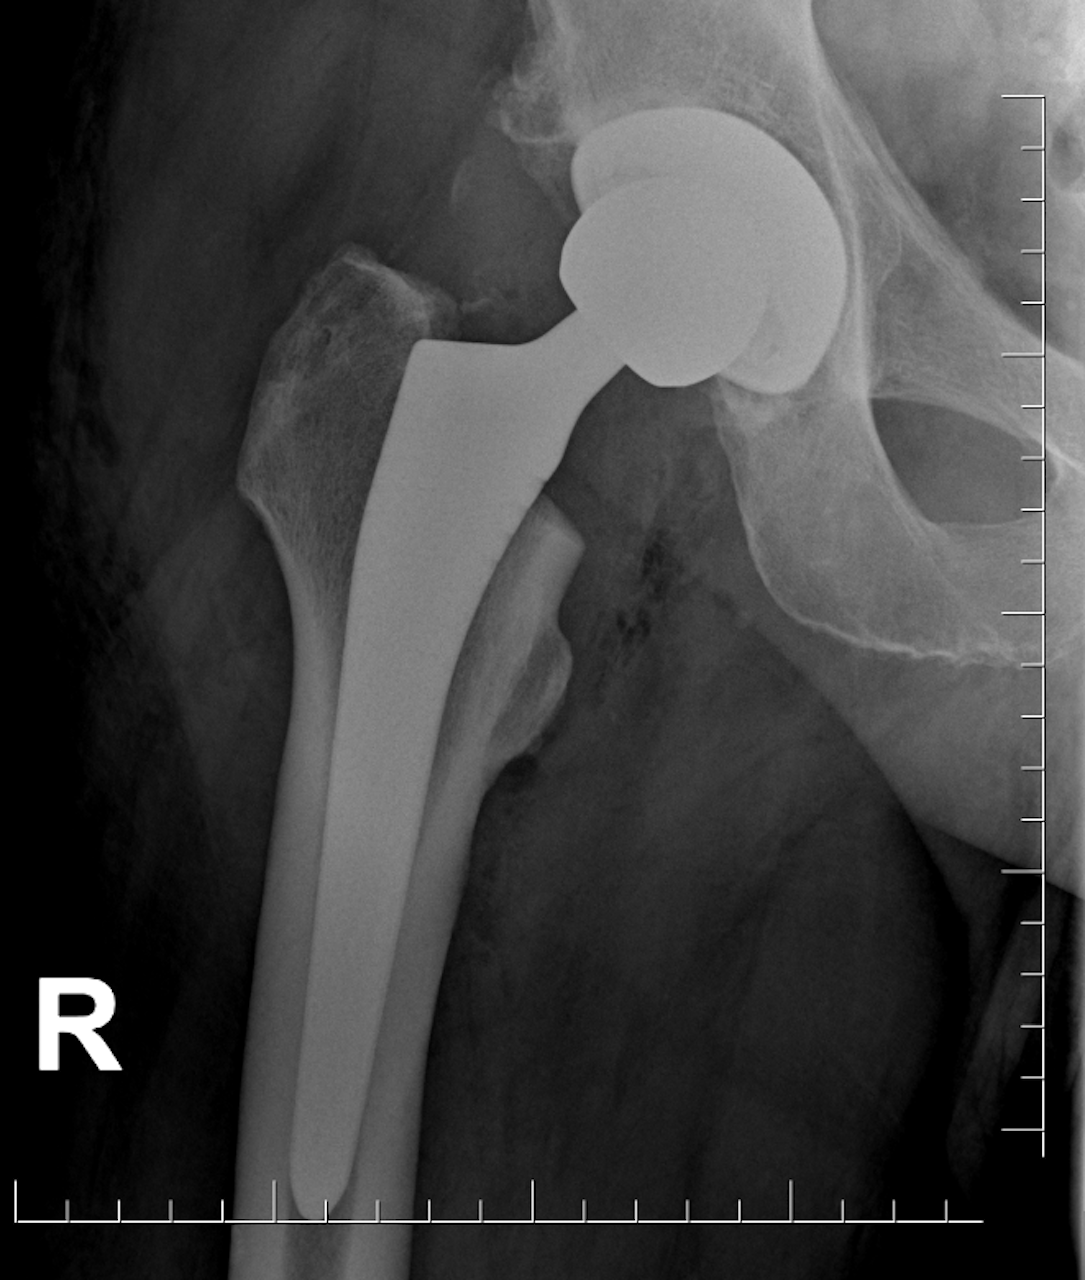

Są bardziej trwałe i lepiej łączą się z kością. Lekarze ze Szpitala imienia Wiktora Degi w Poznaniu wszczepili dwojgu pacjentów opracowane przez siebie endoprotezy stawu biodrowego. Wyprodukowała je polska firma z Białegostoku po wielu testach wykonanych przez lekarzy wspólnie z inżynierami.

endoproteza szpital im wiktora degi - Szpital im. Wiktora Degi w Poznaniu

Fot. Szpital im. Wiktora Degi w Poznaniu